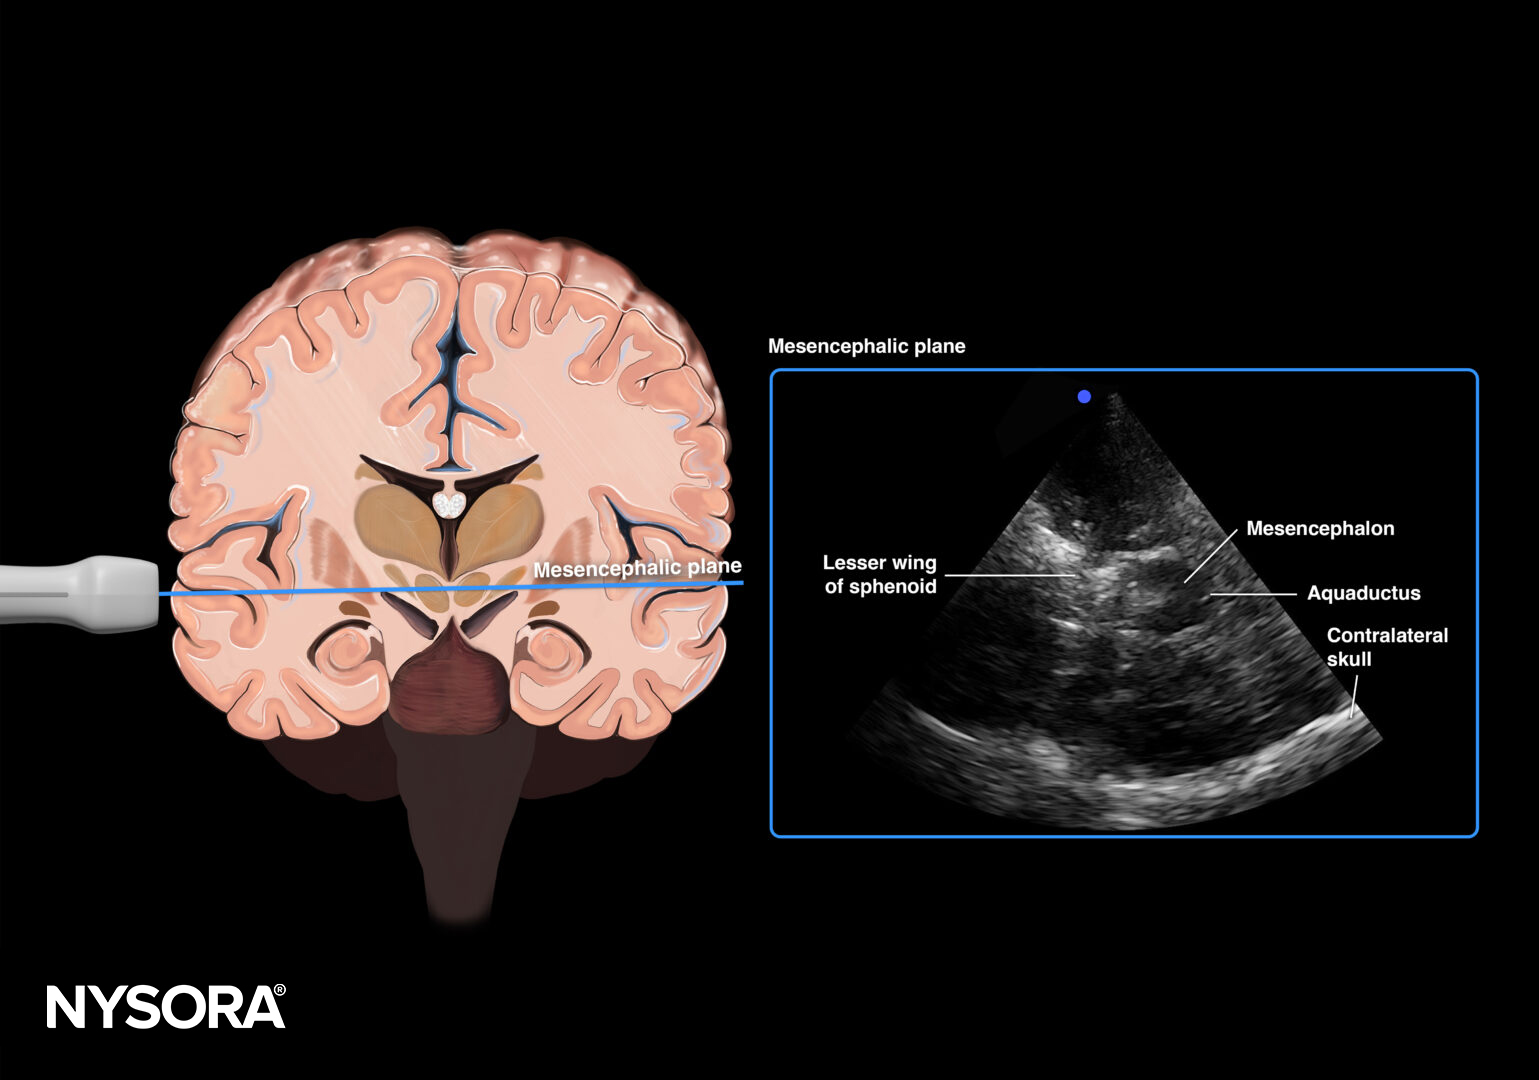

Mesencephalic plane.

- Use the mesencephalic plane and activate pulsed wave Doppler. Position the Doppler gate on the middle cerebral artery (MCA) and trace the flow velocities.